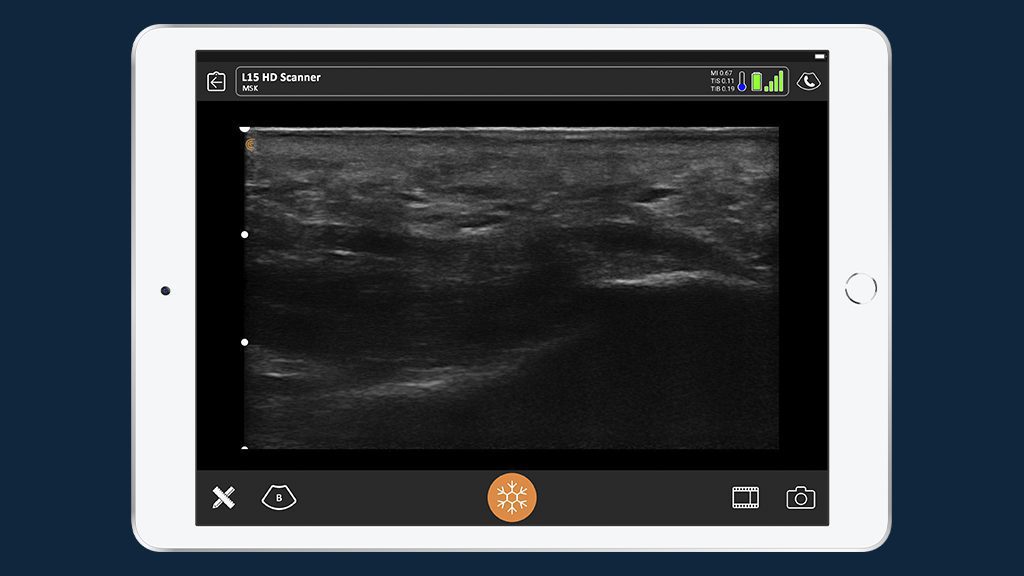

“I learned to use Clarius quickly and really liked its portability,” he says. “It’s lightweight and easy to hold in your hand and doesn’t take up floor space. Image quality is as good or better than the cart-based systems I’ve used. It’s also much faster to power up and down compared to bigger units.”

Dr. Czurylo relies on ultrasound for pathology that isn’t detected on X-Ray. For example, he uses it to see ganglion cysts, tendonitis, plantar fasciitis, bursitis, and ligament sprains.

His patients are happy to follow the exam on the iPad he uses with Clarius. “I can show them in real-time what I’m seeing and I find they’re more confident in my diagnosis.”

Dr. Czurylo uses the Clarius L15HD. Visit our MSK page to learn more about Clarius for musculosketal applications including podiatry. Download our CPT guide for more information about reimbursements for ultrasound guidance. Or contact us today to inquire about getting your very own Clarius HD.